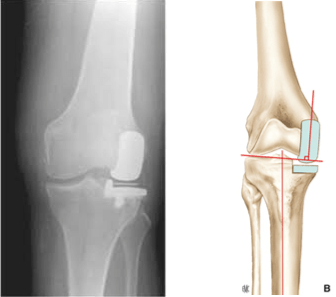

Prótesis uni-compartimental

Se trata de una cirugía en la que sólo se remplaza el compartimento dañado de la rodilla por un implante.

La rodilla puede dividirse en tres compartimentos: fémoro -patelar, fémoro-tibial interno (medial), fémoro-tibial externo (lateral). La prótesis uni-compartimental es una opción si la artrosis afecta solamente a un compartimento de su rodilla.

INDICACIONES:

• Artrosis localizada en un solo compartimento de la rodilla

• Integridad ligamentaria: ligamentos cruzados y ligamentos laterales presentes y funcionales

• Ausencia de sobrepeso mayor

• Deformación en el plano frontal de menos de 5º tras corrección del desgaste fémoro-tibial

• Ausencia de condrocalcinosis articular

• Ausencia de enfermedad inflamatoria como la poliartritis reumatoide

• Edad > 50 años (a valorar caso por caso)

CONTRAINDICACIONES:

• Sobrepeso

• Rotura antigua del ligamento cruzado (reparada o no)

• Deformación en varo o valgo muy importante